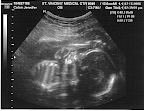

Level 2 Screen - Detailed Ultra Sounds

Today was the completion of level 2 screening at Richmond University Medical Center. We were very excited today, anxiously awaiting to see more detailed ultra sound images of our little one. The ultra sound technician was very nice and really knew what she was doing. The equipment there is much more sophisticated than what our regular Dr. has. The machine has great zoom capability color mapping of blood flow and tools to accurately measure anatomical structures including head circumference.The technician took about 60 snapshots of various anatomy. We saw many of the vital body parts and organs such as the head, brain, heart, arms, hands, legs, feet, liver, kidneys, umbilical cord and mama's uterus (oh and his you know what that proves he's a boy). He was moving around a lot so it took some time to get a snapshot of those tiny toes. The only drawback of the day was that I've had a migraine but I wont get into that, its for another blog post.

We are very happy the technician confirmed everything looks very good from these images.